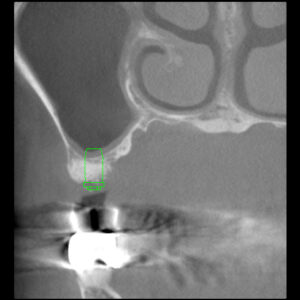

2016年6月にサイナスリフトをおこなった症例(30…

ストレスマネージメントとしての睡眠時のはぎしりは時として、咬合の崩壊をもたらします。 30代であれば、奥歯の再生とスムーズな歯ぎしりの誘導は、精神的にも全身の健康にも及ぼす効果は計り知れません。それほど奥歯の再生は重要です。 上あごの骨が無いところにインプラントを埋入しなければなりません。とる…